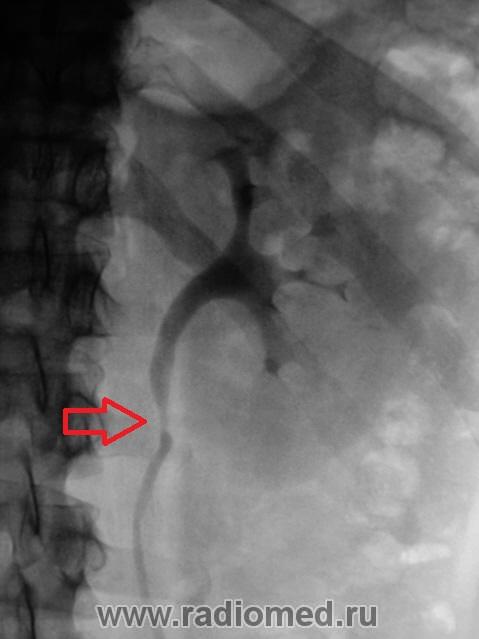

А как насчёт добавочных сосудов?

Такие)